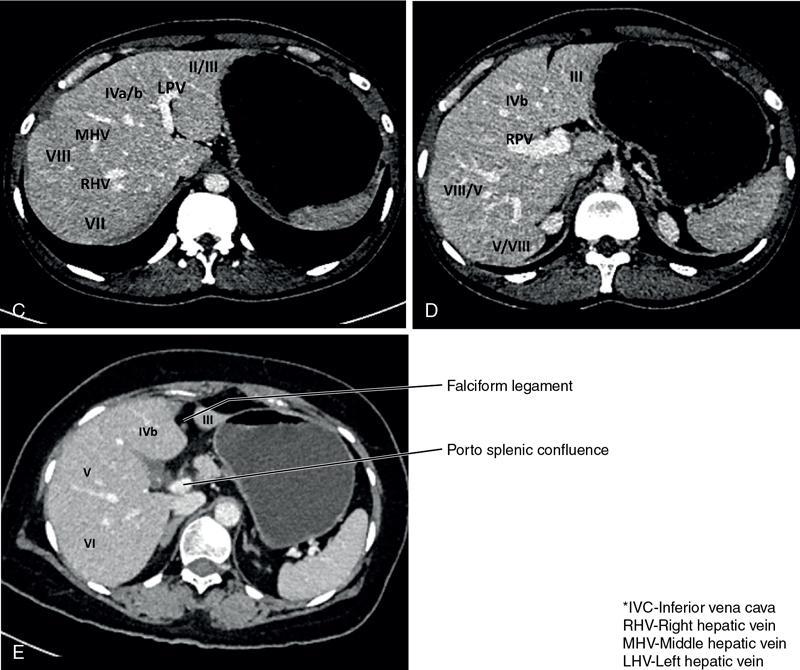

CROSS SECTIONAL ANATOMY OF ABDOMEN Satya Jha NORMAL ANATOMY OF ABDOMEN AND PELVIS Amandeep Singh The two major surfaces: The anterior and posterior layers of the coronary ligament converge on bare area (not covered by peritoneum). Its right and left margins form the right and left triangular ligaments. The right triangular ligament extends toward the diaphragm and separates right subphrenic space from right subhepatic space. The left triangular ligament gives tracts extending to the diaphragm and falciform ligament and does not compartmentalize the left subphrenic space. Ligamentum teres or the obliterated umblical vein is contained in falciform ligament which attaches the liver to anterior abdominal wall. The main portal vein, the proper hepatic artery and the common bile duct are contained within investing peritoneal folds of hepatoduodenal ligament at the porta hepatis (Fig. 7.2.2.1). Liver is divided into eight segments which are functionally independent and have their own vascular supply and biliary drainage. Arterial circulation: The branches of the hepatic artery accompanying the portal veins. Hepatic venous system: The right, middle, and left hepatic veins draining into IVC (Figs. 7.2.2.2 and 7.2.2.3). The gallbladder is a blind pear-shaped muscular membranous sac which is an embryologic derivative of the foregut, is a pouch lying along the undersurface of the liver. The gallbladder fossa is located in the plane of the interlobar fissure, which lies between the right and left hepatic lobes. Its major function is to store and concentrate bile which is produced by the liver. It measures approximately 4 cm in diameter when it is normally distended. Gallbladder is a smaller tubular structure in contracted state. The normal gallbladder wall thickness ranges from 1 to 3 mm. The gallbladder is divided into the fundus, body and neck. Infundibulum is present in the region of neck of the gallbladder, which is called the Hartmann pouch, where gallstones are usually impacted. Intrahepatic biliary radicles (IHBRs) scattered throughout the liver get confluent towards the hilum. They unite to form the right and left main hepatic ducts which further unite to form common hepatic duct (CHD) at the hilum. Common bile duct is formed by the union of cystic duct with common hepatic duct. The main pancreatic duct is joined with the common bile duct to form the ampulla of Vater at the major duodenal papilla (Figs. 7.2.2.4 and 7.2.2.5). Pancreas is located in anterior pararenal space of retroperitoneum anterior to perirenal (Gerota’s) fascia and posterior to parietal peritoneum. It is divided into head, uncinate process, neck, body and tail from right to left. Pancreas lies anterior to portal vein, which marks the point of transition between the body and neck. The region between head of pancreas and second and third parts of duodenum is known as the pancreatic groove. In postnephrectomy cases or with agenesis of kidney or ectopic kidney, pancreas moves posteriorly to partially fill in the empty renal fossa; its soft tissue density should not be mistaken for recurrent tumour. It is located in the pancreatic groove and is bounded superiorly by the duodenal bulb, laterally by second portion of duodenum, inferiorly by third portion of duodenum, medially by superior mesenteric vein and anterior to inferior vena cava. It is a wedge or wedge shaped lying posterior to superior mesenteric artery and vein. It is an imaginary junction between the head and body and lies directly over the junction of the splenic vein and superior mesenteric vein. It is located posterior to the lesser sac and anterior to the aorta, left adrenal gland, left kidney, and renal vessels and runs obliquely upward to the left of the superior mesenteric vessels. It is situated median to the colonic flexure and anterior to the left kidney. It is located in close proximity to the splenic hilum without a notable relation with the body of pancreas. It is seen anterior to the left kidney and median to the colonic flexure. The distal part of the tail passes between the peritoneal layers of the splenorenal ligament (Fig. 7.2.2.6 and 7.2.2.7).

Liver

The bismuth and couinaud classification of liver

Couinaud

Traditional

Segment I

Caudate lobe

Segment II

Lateral superior segment of left lobe of liver

Segment III

Lateral inferior segment of left lobe of liver

Segment Iva

Medial superior segment of left lobe of liver

Segment IVb

Medial inferior segment of left lobe of liver

Segment V

Anterior inferior segment of right lobe of liver

Segment VI

Posterior inferior segment of right lobe of liver

Segment VII

Posterior superior segment of right lobe of liver

Segment VIII

Anterior superior segment of right lobe of liver